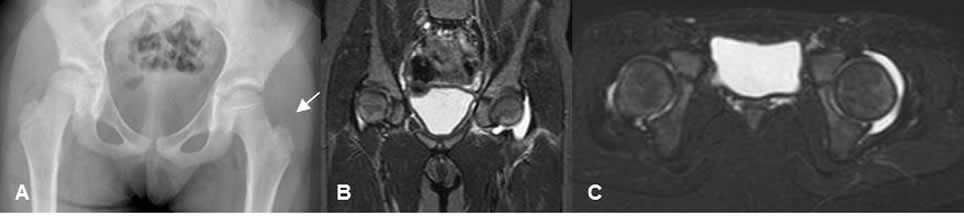

Fig 155. Derrame articular.

Fig 156. Derrame articular.

A: Rx AP. Desplazamiento lateral del cojinete graso glúteo, que hace sospechar derrame articular.

B: RM coronal y C: RM axial en STIR. Se confirma el derrame articular, por artritis infecciosa.